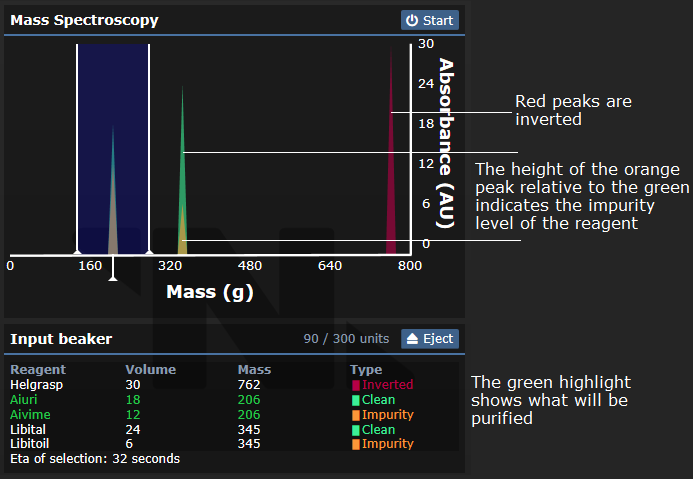

Может определять уровень примесей добавленных в него реагентов, что делает его одним из лучших способов определения чистоты реагента в начале раунда. См. ниже:

HPLC также позволяет очищать реагенты до их стандартной чистоты (обычно 75%). Для его работы требуется время. Инвертные реагенты не могут быть очищены, однако любые химикаты, пропущенные через систему потребуют время на обработку. Пока аппарат занять другой работой, вы не можете использовать масс-спектрометрию на нем.

Нажатие левой кнопки мыши позволяет взаимодействовать с входной колбой, установленной в хроматографе, нажатие левой кнопки мышь с зажатой кнопкой alt позволяет извлечь колбу. С помощью правой кнопки мыши можно также взаимодействовать с выходной колбой. Для своей работы машина требует обе колбы, хотя проводить анализ она может и с одной входной колбой.

Иконка также показывает, в каком состоянии находится прибор прямо сейчас - гистограмма на экране показывает, что он анализирует входной стакан, синусоидальная волна показывает, что в данный момент происходит очистка, а пустой экран означает, что входной стакан либо пуст, либо удален.